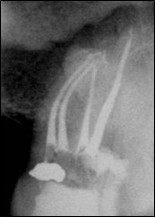

Poniżej przedstawiono zdjęcie radiologiczne górnego zęba trzonowego po leczeniu endodontycznym. W jednym z korzeni policzkowych widoczne dwa kanały. Podaj jaki to typ wg Wein’a: